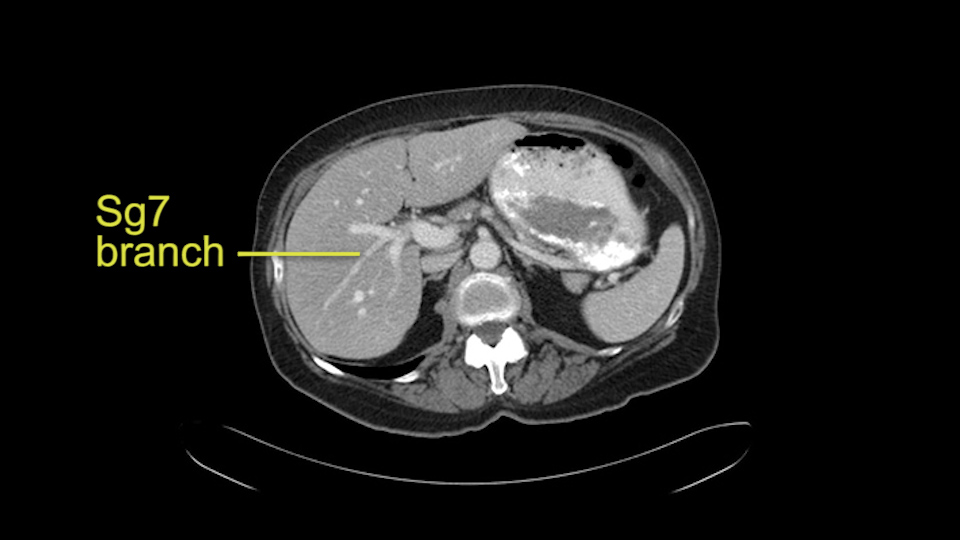

This patient has an interesting minor anomaly with what looks like a Segment 7 portal vein coming off close to the bifurcation of the right portal vein but again if I was doing a right lobe which is my plan, this wouldn’t be an issue.

![[Sg7 branch]](jpg/preop_sg_moment5.jpg)